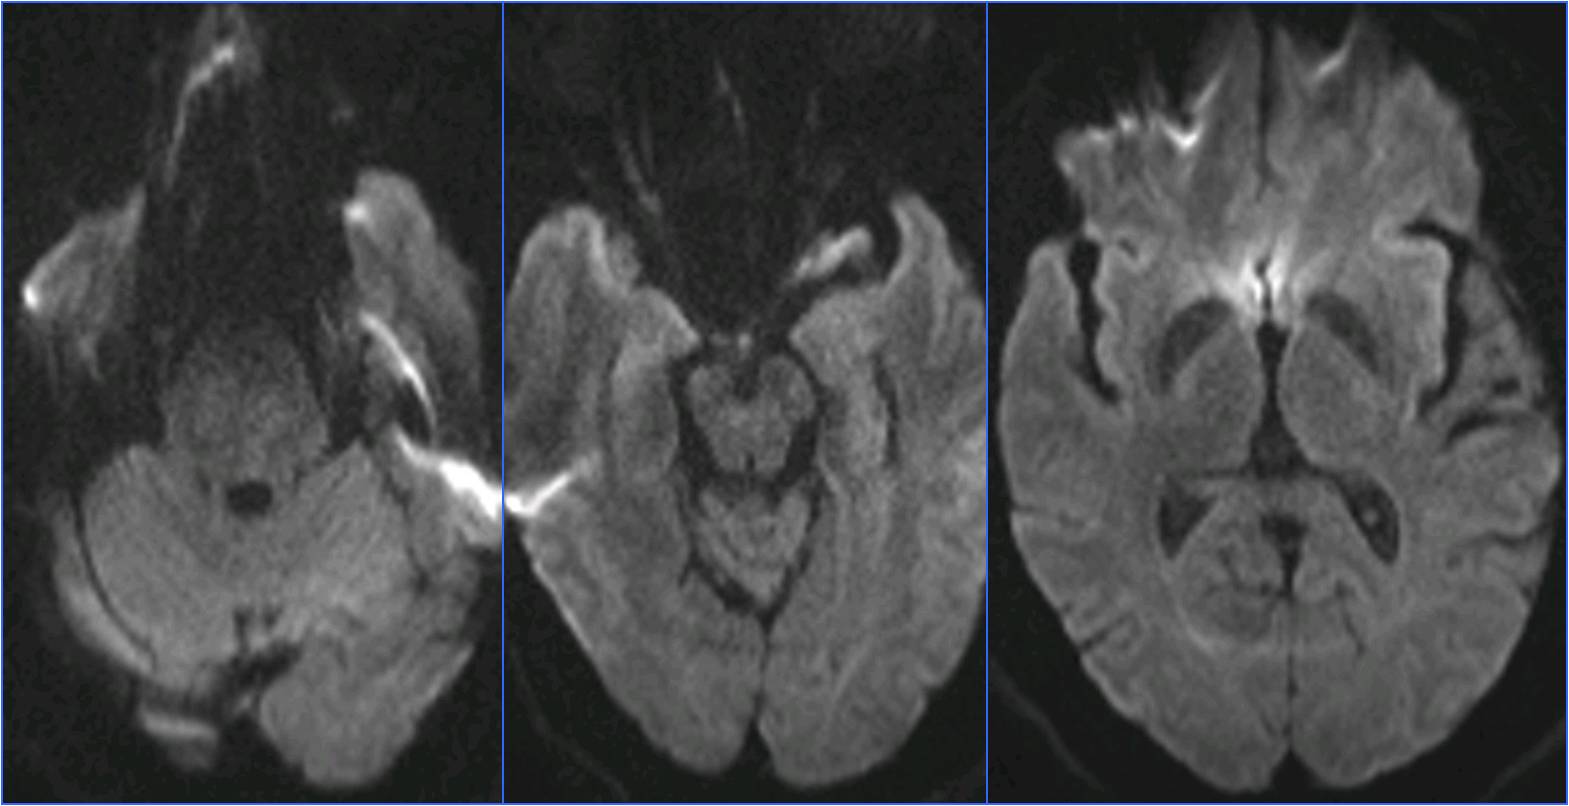

▼于基底动脉远端及双侧大脑后动脉,分次给予阿替普酶共计5mg。

▼溶栓后MRI